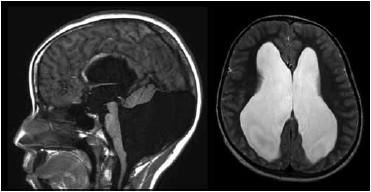

Paciente do sexo feminino, 8 anos, há um mês sofre de cefaleia holocraniana diária associada a vômitos, com melhora parcial com analgésicos. Ao exame, apresenta papiledema. Realizou a ressonância de crânio a seguir.

O diagnóstico é hidrocefalia secundária